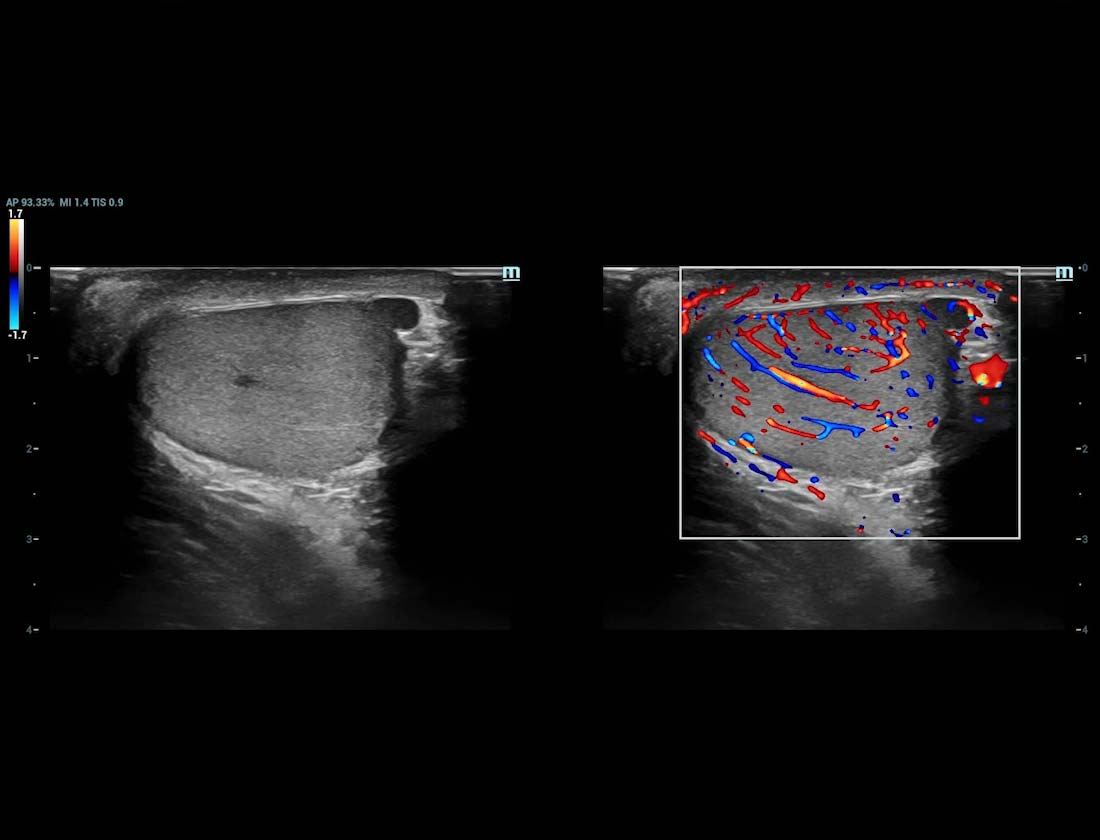

Angiografia ultramicroscû°pica (Ultra Micro Angiography, UMA)

UMA aumenta a confian?a diagnû°stica ao expandir a visibilidade dos fluxos sanguûÙneos atûˋ o nûÙvel de vasos minû¤sculos, com sensibilidade e resolu??o superiores.

UMA ã TestûÙculo

Glazing Flow sUMA em varicocele